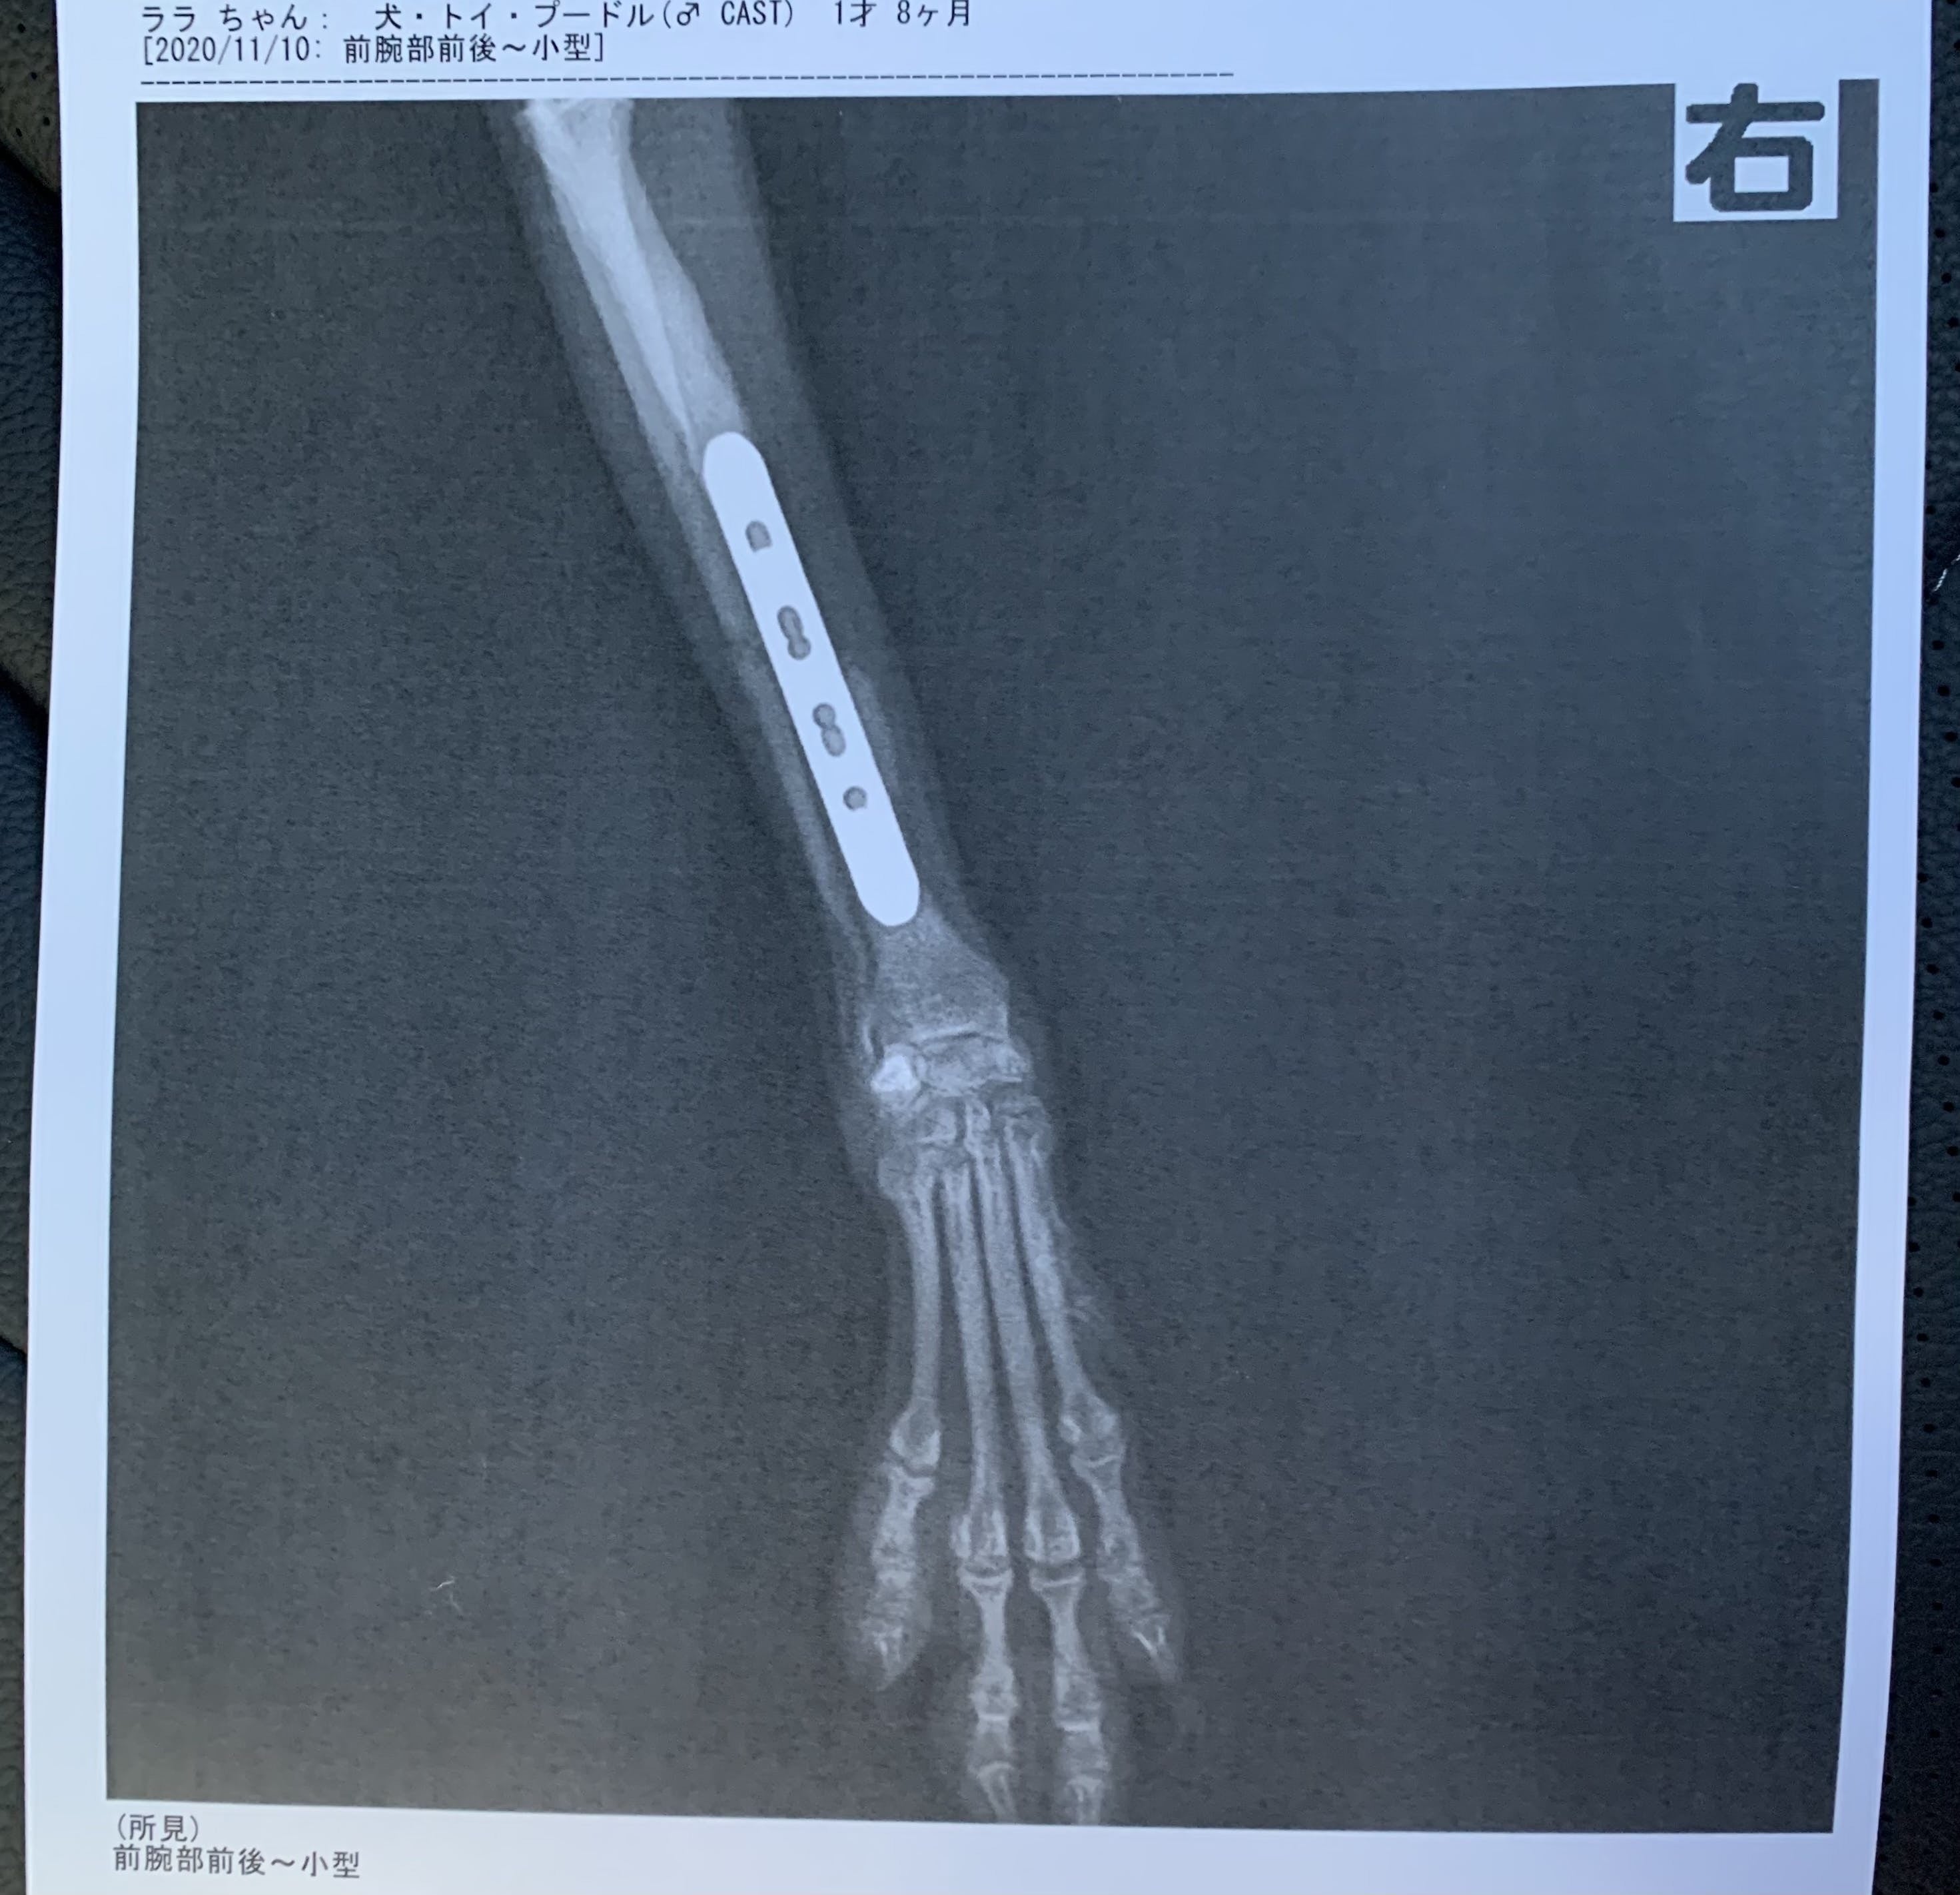

現在愛犬ララは骨折してからボルドを4本入れ入院しています。どうか皆様のご協力いただけませんでしょうか。

右前足が骨折してしまい食事を全く食べていない状況なので点滴でまかなってご飯を食べてもらってます。

現在ボルドを右足に4本入れて固定していて、12月〜来年の1月に骨が治っていれば2つのボルドを取り除く手術をします。状況を見て完治していれば残りの2つのボルドを取り除く手術をします。

今回の緊急手術と全身麻酔やX線検査と入院代約47万2千円

経過観察のレントゲン代や再度する手術や入院代、お薬代などで約30万円かかる予定です。皆様にご協力いただきたく

実際にボルドでとめている写真です。

現在ボルドを右足に4本

12月〜来年の1月に2つのボルドを取り除く手術をします。

ララの様子を見て完治していれば残りの2つのボルドを取り除く手術をします。